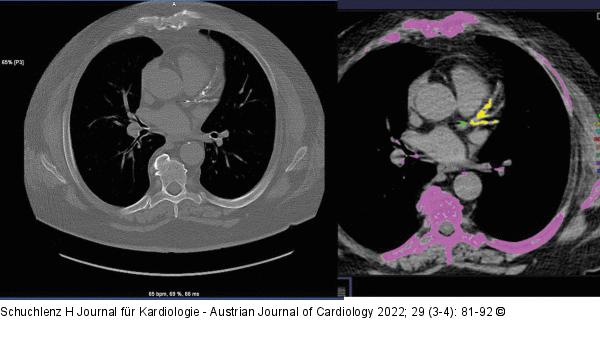

Abbildung 1: Verkalkung Das Bild zeigt ausgeprägte Verkalkungen (Agatston-Score > 300) im Bereich des LM, der LAD und der LCX, dies sagt aber nichts über den Stenosegrad oder über das Vorhandensein von nichtkalzifizierten Plaques aus. LM: Left Main; LAD: Left Anterior Descending Artery; LCX: Left Circumflex Artery |

Das Bild zeigt ausgeprägte Verkalkungen (Agatston-Score > 300) im Bereich des LM, der LAD und der LCX, dies sagt aber nichts über den Stenosegrad oder über das Vorhandensein von nichtkalzifizierten Plaques aus. LM: Left Main; LAD: Left Anterior Descending Artery; LCX: Left Circumflex Artery |